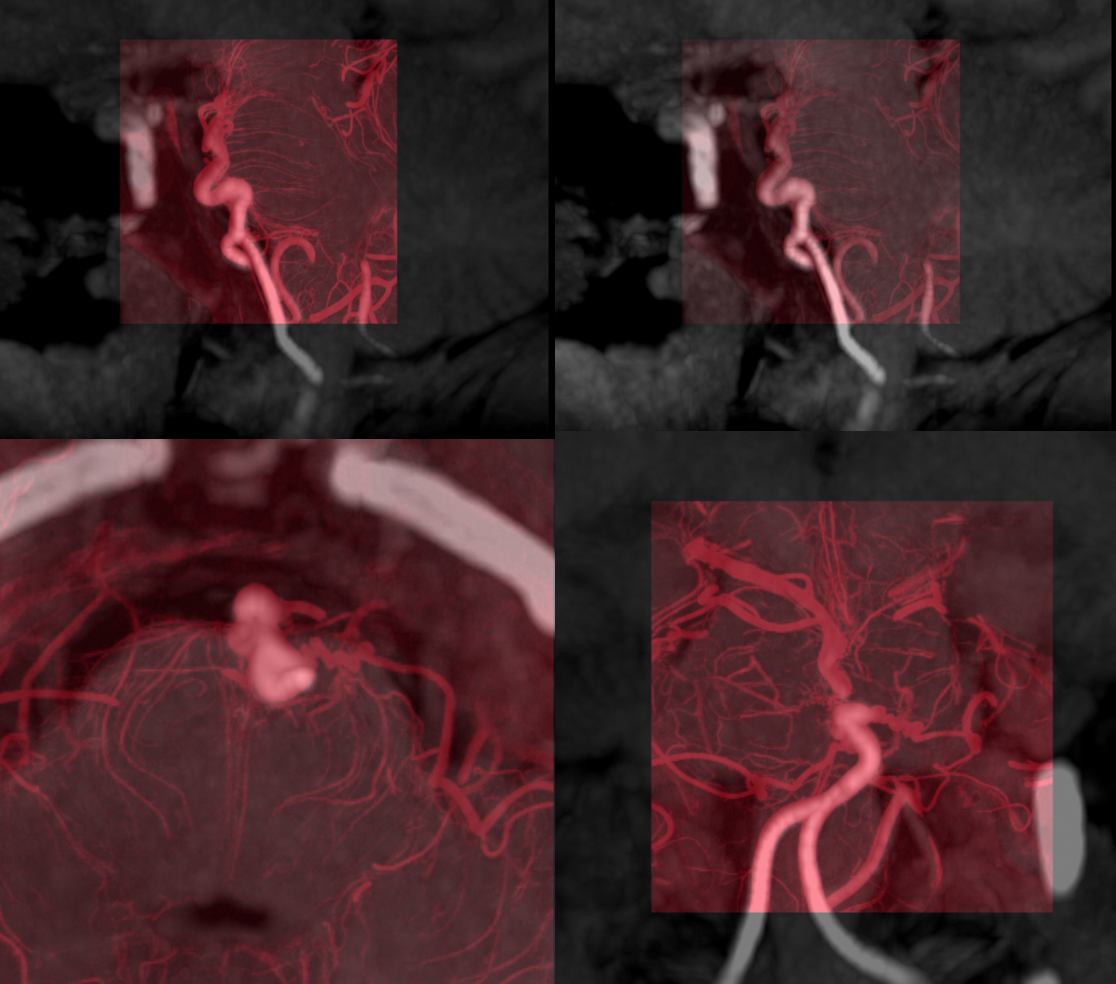

Here is an ICA/PCOM/PCA example. Very rare.  May attest to embryoic origin of the PCA as an anterior circulation vessel aka “Caudal Ramus” (see embryology section)

CTA is probably the best modality for these – not how i usually feel, with modern MRA being first choice for most anything. However it is very easy to miss the bulk of finding on MRA, whereas CT shows calcifications and dolichoectasia very nicely.

Here is a CTA of an asymptomatic patient. Notice tram-track calcifications and tortuosity in distal ICA/PCOM/PCA

MRA is rather bland. If anything would suspect occlusive /stenotic disease here

Typical enlarged vessel caliber on T2. Sometimes the bulk of enlargement is a thick, calcified wall, as in this case. Sometimes the lumen is also dilated. Gradient echo sequences are very useful here for picking up calcs

You can see how CTA is probably the single best modality here. MRA could miss this. MRI gives rise to suspicion of AVM or fistula, especially when quality of imaging is inferior